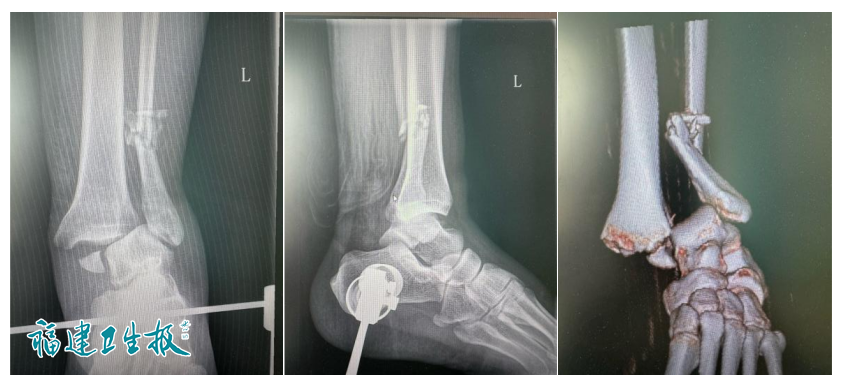

球友见情况不对,赶紧将小刘送至福建医科大学附属第一医院骨科。王海副主任医师接诊后为他拍片检查,结果显示:右踝关节骨折、右侧下胫腓联合分离。

▲图片显示小刘骨折错位严重,同时还伴有严重的韧带损伤

王海告诉小刘,骨折移位严重,需手术治疗,术后三个月不能负重,还要配合康复治疗,才有可能恢复踝关节功能。